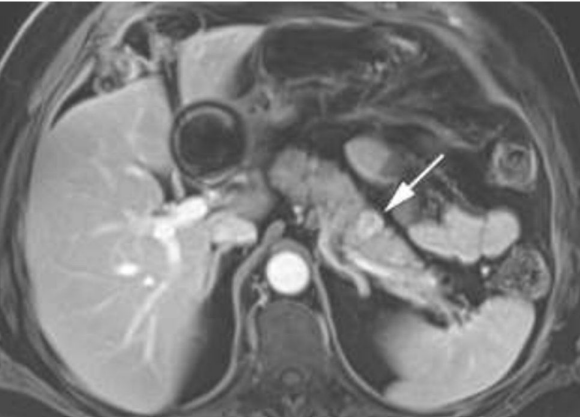

Mulher 57 anos. Dor epigástrica leve e dispepsia há 3 meses. Realizou USG que mostrou lesão mal definida em cauda pancreática. Após avaliação cirúrgica, fez uma RM do abdome superior sugestiva de tumor neuroendócrino pancreático (PNET) de 3,8 cm (Imagem abaixo). EDA normal. Sem sintomas de disglicemia ou diarreia.

Em relação à conduta e diagnóstico (estadiamento), assinale a alternativa CORRETA.